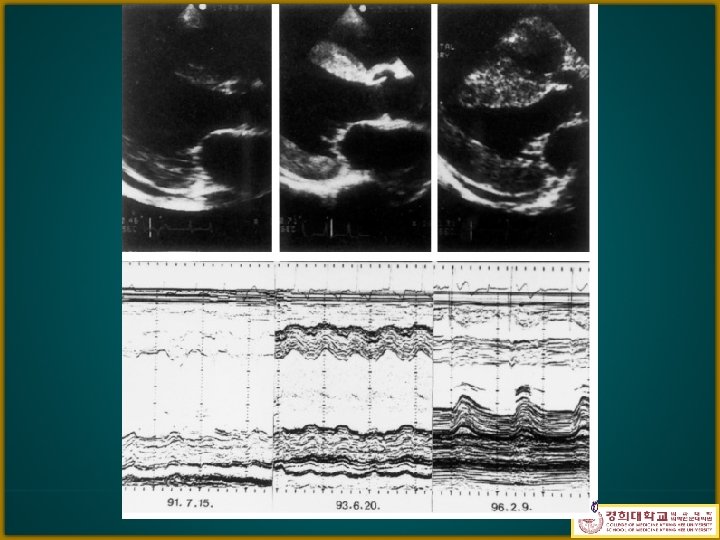

Echocardiography